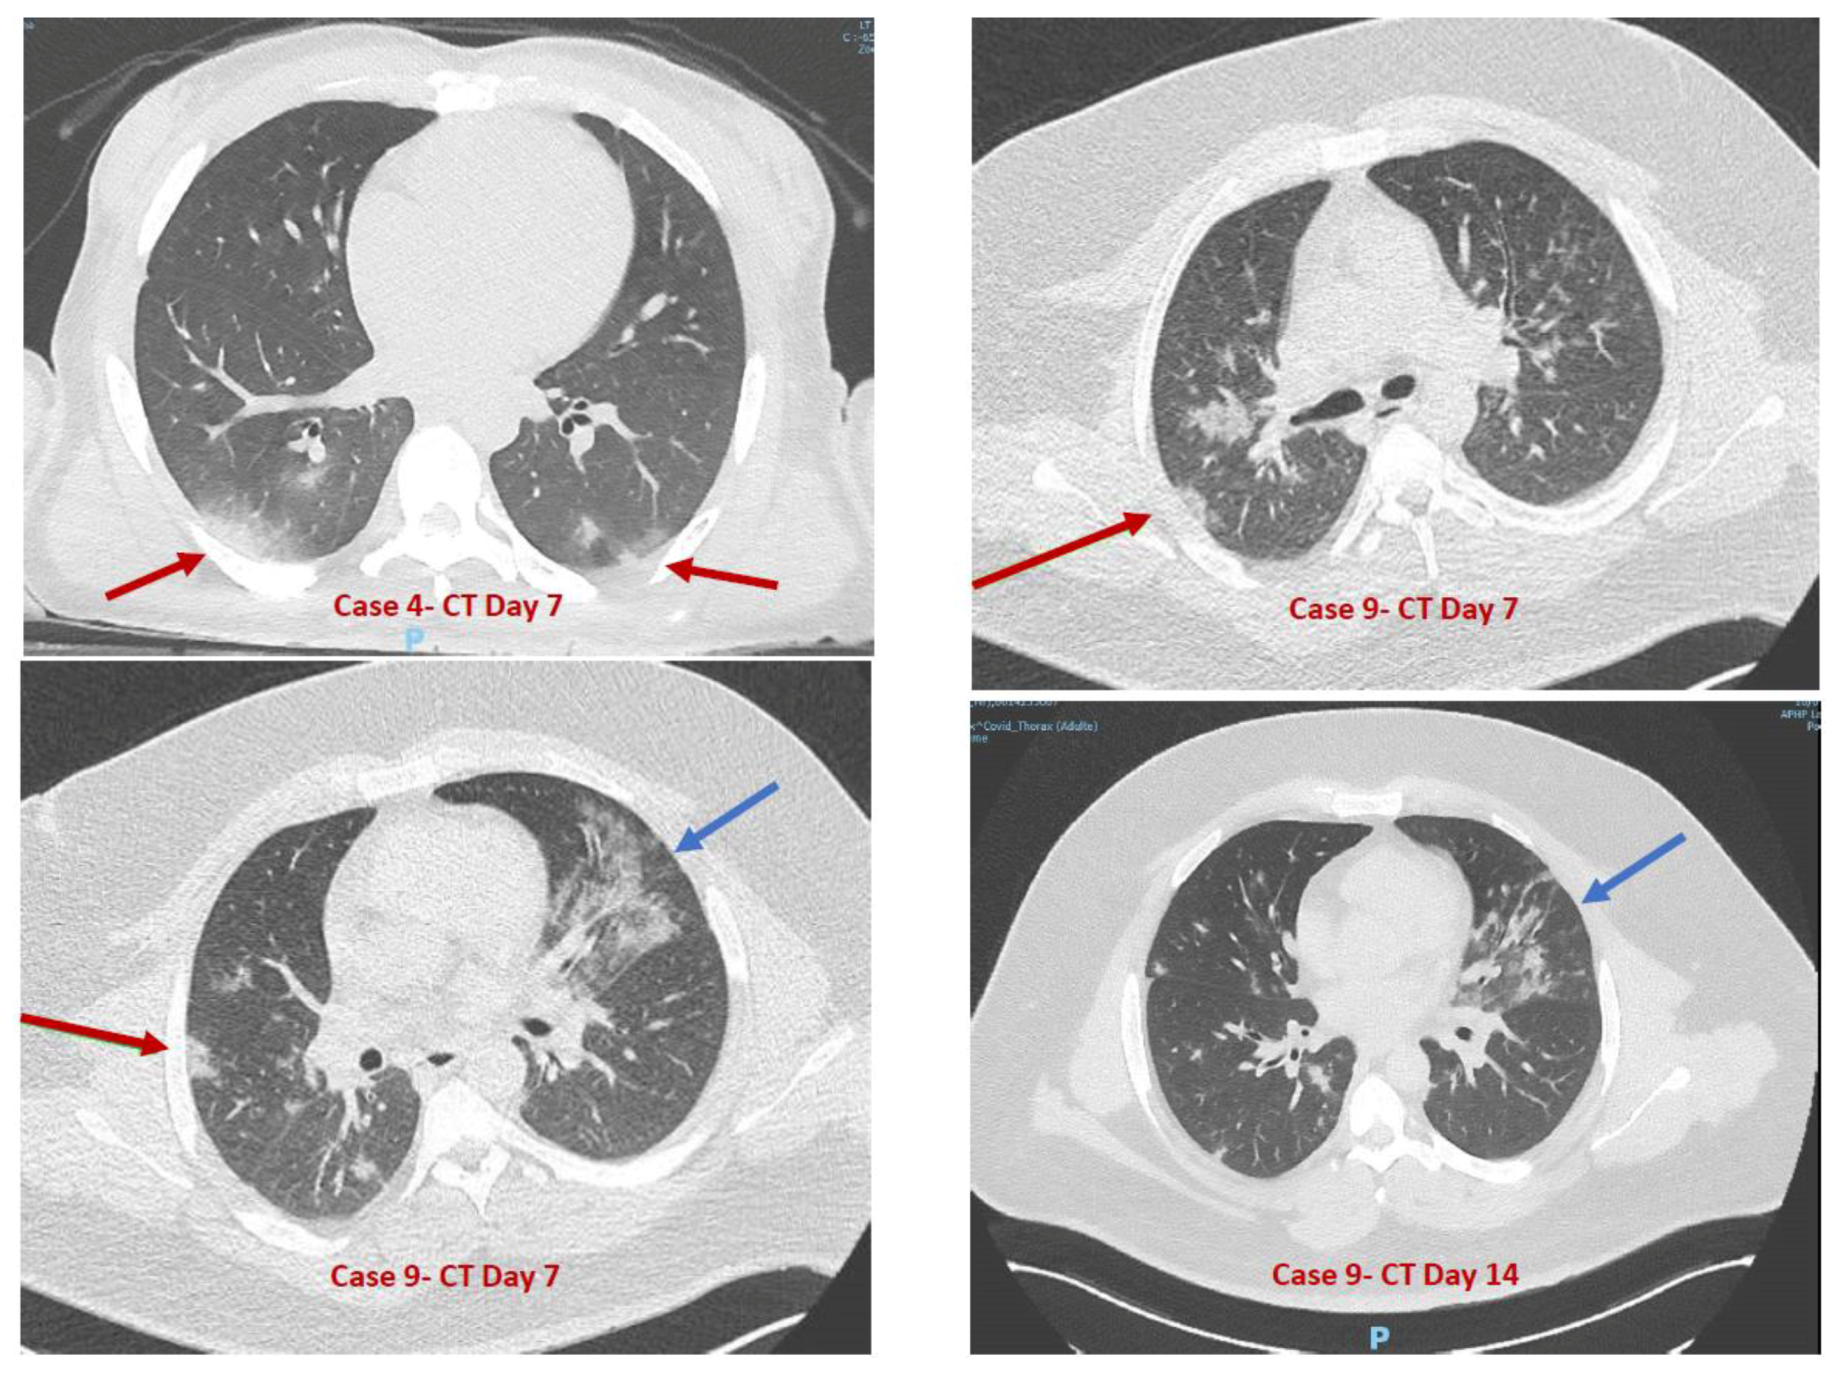

| Case 9 | M | 28 | Limited social-emotional reciprocity and nonverbal communicative behaviors | No | No | Nonverbal | Level 3 | Severe ID | No | Epilepsy, class III obesity (BMI = 55), HBP | Yes (J1; <36 h) | No | Dry cough (J1; 2), polypnea (J1; >9 days) needing oxygen | No | No | Epilepsy (J7, 1 episode) | No |

| Case 9 | Yes | Negative | Positive | Yes | No | At Day 6: Elevated C-Reactive Protein (22.4 mg/L), Aspartate AminoTransferase elevation (×1.5 N) | Yes |